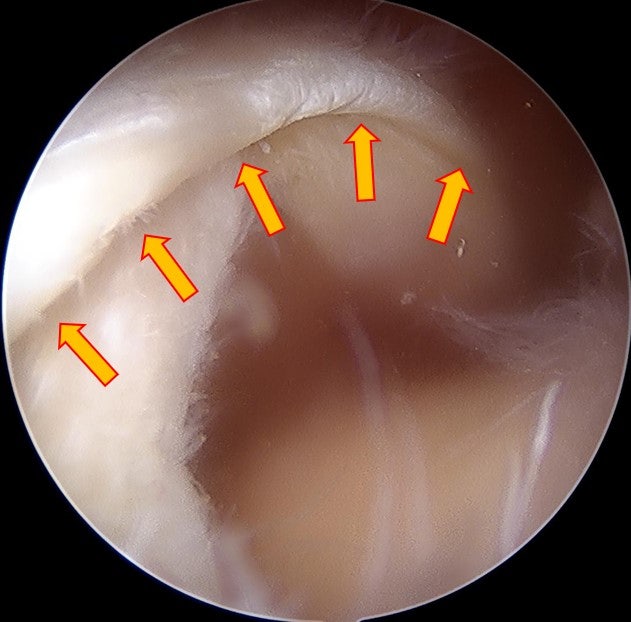

수술을 원래 계획했던 대로 allomend 를 이용하여 회전근개 봉합술 및 봉합술을 시행하였습니다. 수술 직후 MRI 영상으로 확인해 보았습니다.

수술 후 3개월차에 다시 MRI 영상을 확인해 보았습니다.

광범위한 회전근개 파열이 있는 경우 완전히 해부학적으로 복원되지 않는 경우가 있습니다. 할 수 있는 만큼만 봉합을 한 경우 회전근개의 부착 부위가 원래의 해부학적으로 부착하는 것보다 적어지기 때문에 재파열이 발생할 가능성이 있고 회전근개의 기능의 회복도 잘 되지 않을 가능성이 많습니다. 이러한 경우 인조인대를 이용하여 보강술을 해주면 원래의 모양대로 해부학적인 복원이 가능하게 됩니다. 인조인대를 이용한 보강술을 술기가 복잡하고 어렵게 때문에 이러한 수술을 하는 병원이 많지는 않습니다. 모든 수술의 원칙은 손상된 조직의 해부학적인 복원입니다. 이를 할 수 없는 경우라도 최대한 근접하게 복원하는 것이 좋은 결과를 위해 매우 중요하다고 생각합니다. 환자분은 현재는 거의 정상적으로 활동하고 계시며 매우 만족하며 생활하신다고 합니다. 해부학적으로 복원 불가한 광범위 회전근개파열도 정상으로 회복될 수 있습니다!!!